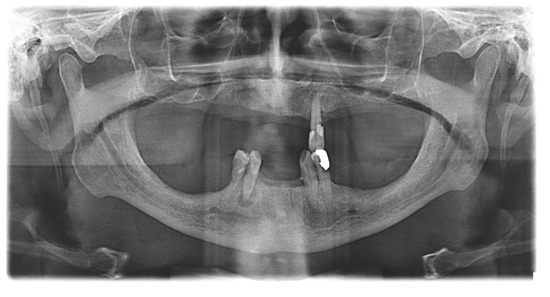

| Hemostatic Disease/Type of Medicine | Patients | Implants |

|---|---|---|

| Warfarin 5 mg | 23 | 86 |

| Dabigatran 75–110–150 mg | 8 | 26 |

| Apixaban 2.5–5 mg | 4 | 18 |

| Rivaroxaban 2.5–10–15 mg | 8 | 28 |

| Edoxaban 30–60 mg | 3 | 10 |

| HP | 4 | 13 |

| VWD | 2 | 7 |